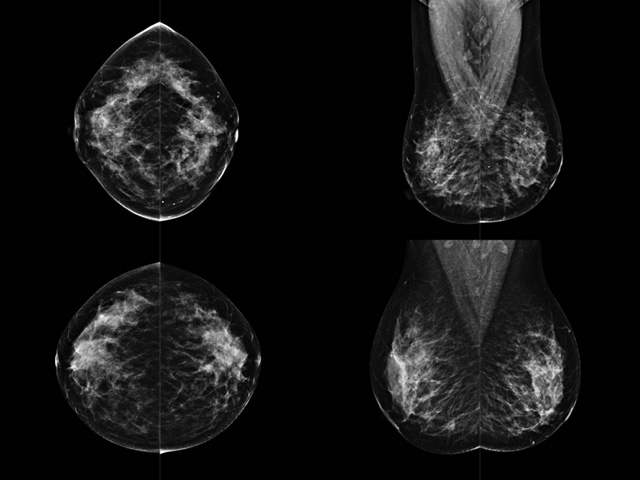

乳腺DR成像設(shè)備中非晶硅跟非晶硒兩種平板探測(cè)器。更要提供優(yōu)質(zhì)的圖像質(zhì)量乳腺的組織結(jié)構(gòu)與厚度各不相同,減少重拍率輻射劑量,,乳腺的主要構(gòu)成組織均為軟組織結(jié)構(gòu),組織之間密度十分相似,缺乏天然對(duì)比度。選擇軟X線攝影技術(shù)獲得良好對(duì)比度的乳腺結(jié)構(gòu)影像。增加各組織對(duì)X線的吸收差異。乳腺攝影測(cè)和分類(lèi),平板探測(cè)器的像素尺寸范圍應(yīng)在50到100μm之間。特別是微鈣化灶可以小到100到200μm,平板探測(cè)器都必極小微鈣化灶進(jìn)行成像。

乳腺DR是利用X光來(lái)做檢查,在一瞬間將被檢測(cè)到的位置投影出來(lái),因?yàn)槭撬查g的輻射,所以只需要0.5秒的時(shí)間。因此對(duì)病人的輻射很低,大約是0.023mSv,比國(guó)家的標(biāo)準(zhǔn)要低得多。DR系統(tǒng)由 X線、發(fā)生裝置、直接轉(zhuǎn)換平板探測(cè)器、系統(tǒng)控制器、影像監(jiān)視器、影像處理工作站等組成。能檢查胸腔積液、肺結(jié)核、大葉性肺炎、肋骨骨折等。心室增大、主動(dòng)脈擴(kuò)張、主動(dòng)脈瘤等心臟病。腹部病變,如腸梗阻、腸穿孔等,DR上可見(jiàn)液氣平面、膈下游離氣腫。DR表現(xiàn)不正常,要結(jié)合臨床表現(xiàn)、體征、癥狀等綜合分析,結(jié)合CT、彩超、血液分析等,才能作出正確的判斷。